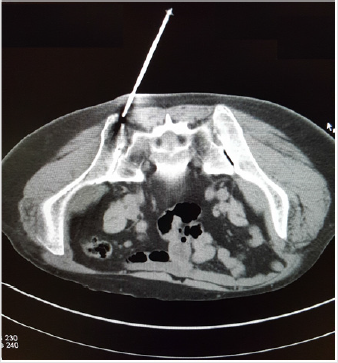

Once the needle was stabilized (locked) in the bone the patient was moved back into the scanner to visualize whether the tip of the needle was in the correct position. Although such verification is not always necessary, we utilized this procedure as a precautionary measure. Once this was affirmed the patient was again moved out of the scanner and a routine bone marrow aspiration was performed using a standard bone marrow aspiration needle [10]. Following bone marrow aspiration, a small incision was made over the marked area with a surgical scalpel to allow for the passage of the standard (11 gauge) bone marrow core biopsy needle [11]. The biopsy needle with the stilette in place was then advanced slowly through the incision, pointing towards the anterior superior iliac spine and when the posterior iliac crest was reached it was then penetrated by gentle rotary motions of the needle. Once the cortex was penetrated the stilette was then removed with one hand while holding the needle in place with the other. The biopsy needle was then advanced with slow, steady and controlled clockwisecounterclockwise rotary motions until an adequate depth (about 20-25 mm) was reached (Figure 3).

Figure 3: A CT image shows the tip of an 11-gauge Islam bone marrow biopsy needle accurately placed over the posterior ilium near the posterior iliac crest before being advanced into the marrow cavity.